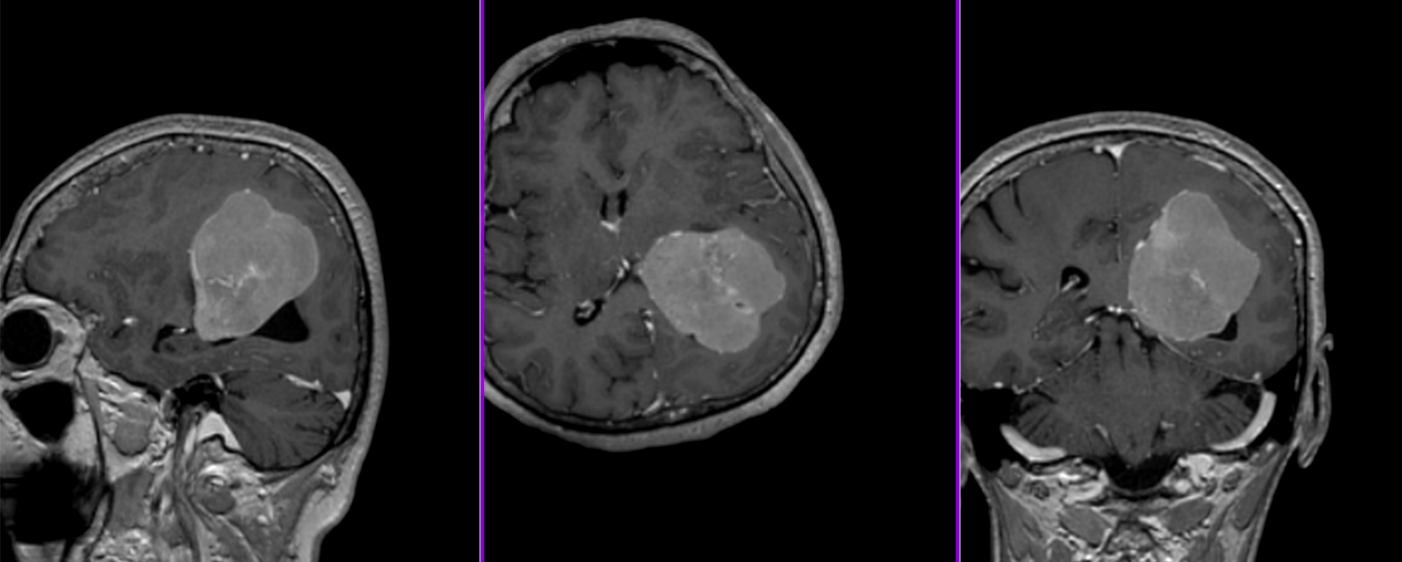

Meningiom olfactiv – RMN postoperator

- RMN – cea mai completă investigație, oferă detalii despre relația cu țesutul cerebral, vasele de sânge și nervii Captarea substanței de contrast este deosebit de importantă.